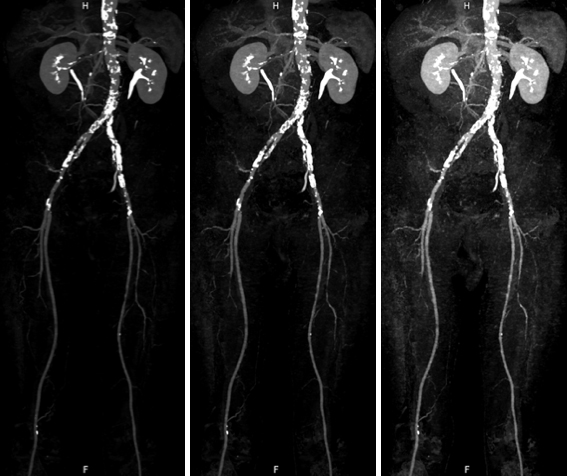

非造影心臓MRI

腎臓の機能が低い場合には、造影剤を用いる冠動脈CT検査は出来ません。MRIでは、造影剤を使用しなくても冠動脈や心臓の機能、心筋の性状を評価する事ができます。

非造影下肢動脈 MRA:造影剤を使用せずに腹部から下肢動脈が描出されており,左浅大腿動脈に狭窄(矢印)を認めます。